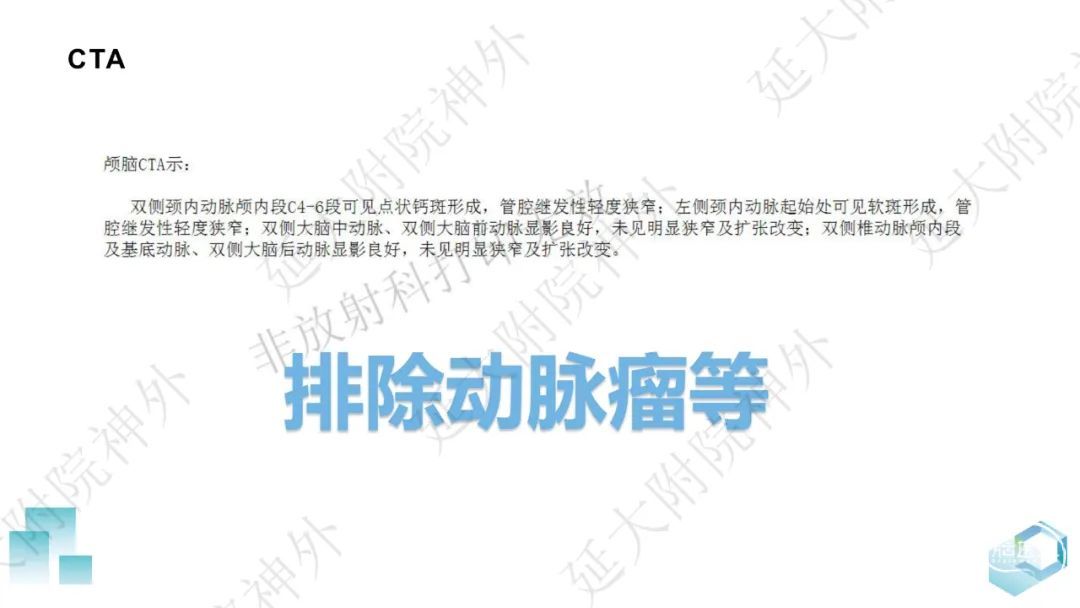

今天为大家分享的是《监测有道丨颅脑创伤-神经重症周刊》第332期,由延安大学附属医院神经外科贾云峰主任医师带来的:左侧基底节区出血破入脑室一例神经内镜下血肿清除术,欢迎阅读、分享。